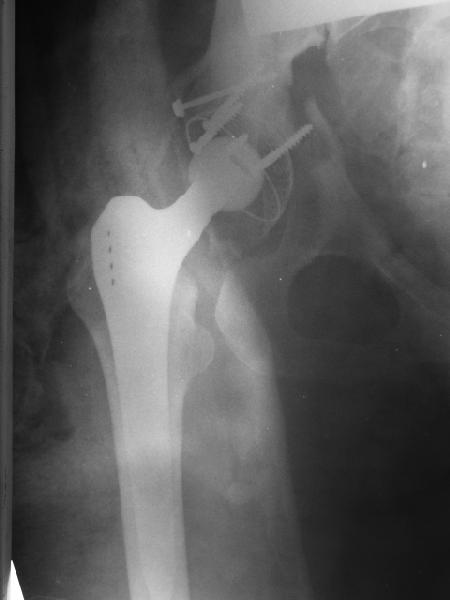

Обратились коллеги из городской больницы N36. Женщине 39 лет по поводу диспластического коксартроза около года назад выполнено эндопротезирование правого тазобедренного сустава. Вчера ехала на госпитализацию на протезирование второго сустава, и попала в аварию.

Получила поперечный перелом правой вертлужной впадины (снимок прилагается) с переломом ветвей лонной кости на другой стороне (inletview также в приложении), а также поперечный перелом дистального метафиза бедра на этой же стороне. Что посоветуете в отношении протеза и впадины? Спасибо заранее.

A colleague of mine from another hospital requests opinion. A female 39 years old was operated ~1 year ago - right side THA for hypoplastic hip. Yesterday she was going to the hospital for THA ofthe second hip but got involved in a car accident.She admitted with right acetabular and left rami fractures (images attached). Also trasverse fracture of the right distal femur.Seeking your advice regarding the acetabular fracture. THX!

Ножка Алтимед, а чашка цементая???? Хороший гибрид. Насколько позволяет рентгенограмма, можно судить, что чашка стабильна (за счет цемента и арматуры в виде винтов). Нужен постельный режим не менее 6 недель.

Ситуация редкая и нестандартная. Складывается впечатление, что эндопротез вертлужной впадины стабилен. Я бы выполнил остеосинтез перелома в/впадины реконструктивной пластиной. Эти переломы срастаются хорошо.

Установлена RM-чашка бесцементная,ножка тип Цвайммюллер производства Мathys,сделана костная пластика.В настоящее время необходим остеосинтез реконструктивной пластиной без удаления чашки,так как чашка стабильна.

ДВ> остеосинтез реконструктивной пластиной без удаления чашки,так как

ДВ> чашка стабильна.